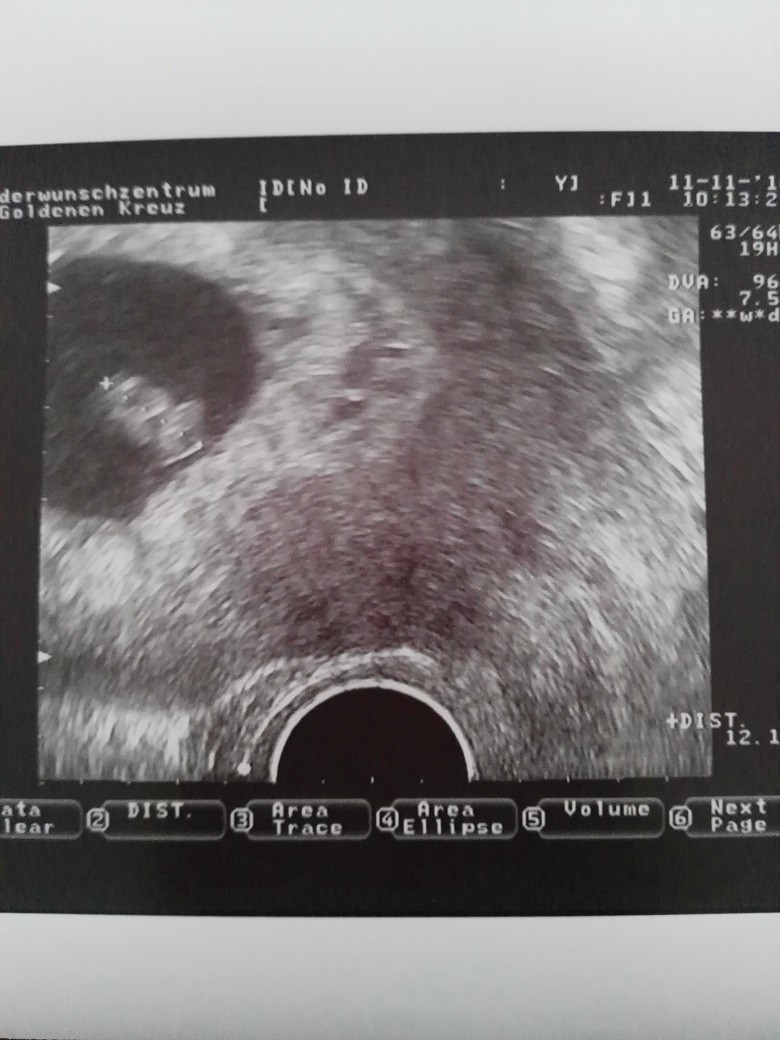

Cudny widok

Szczęście ma 12 mm, wszystko prawidłowo się rozwija.

Dziękuję Wam za kciuki i życzenia. Mam nadzieję, że każda z Was przeżyje tę cudowną chwilę.